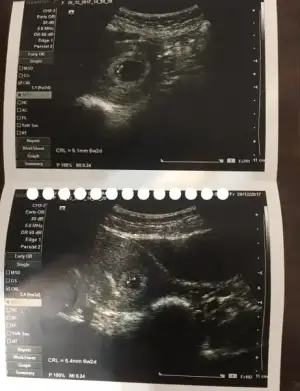

Yükleyebildim mi bilmiyorum ultrason görüntüsünü ilk kontrolüme bugün gittim. Nihayet gidebildim:) Keseyi gördüm kalp atışlarıda görülüyor dedi doktor ama dinletmedi. Ultrasondan oldum olası bişey anlamam.doktordan geldiğimden beri kağıtla bakışıp duruyorum:anneadayı::KK200:

Ben bebeği görüyorummmm. Ay miniklerimiz yaaa insan tuhaf oluyor :)